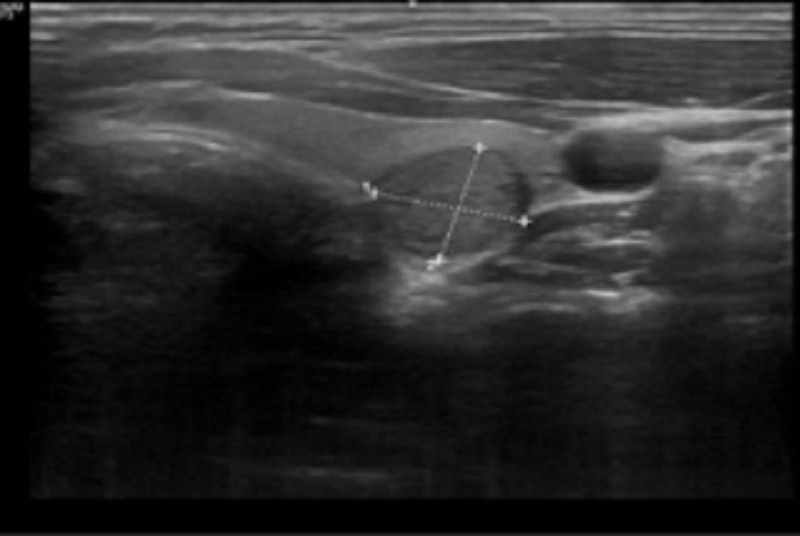

| Siêu âm tuyến giáp nhu mô có nhân giảm âm - dấu hiệu nghi ngờ ác tính. |

Kết quả siêu âm tuyến giáp cho thấy xuất hiện nhân giảm âm kích thước khoảng 10,4 x 11,6 mm, có đặc điểm chiều cao lớn hơn chiều rộng và nằm sát vỏ bao tuyến giáp, đây là dấu hiệu nghi ngờ ác tính. Bệnh nhân được chỉ định chọc hút tế bào bằng kim nhỏ.

Để chẩn đoán chính xác bệnh lý tuyến giáp, bác sỹ thường kết hợp nhiều phương pháp. Trong đó, siêu âm tuyến giáp là công cụ quan trọng hàng đầu, giúp xác định kích thước, vị trí, cấu trúc và các đặc điểm nghi ngờ của nhân như độ phản âm, bờ viền, tình trạng vôi hóa hay mức độ tăng sinh mạch máu.

Kết quả được phân loại theo hệ thống ACR TIRADS 2017 từ mức 1 đến mức 5. Siêu âm cũng đóng vai trò hướng dẫn chọc hút tế bào bằng kim nhỏ, giúp tăng độ chính xác và giảm tỷ lệ lấy mẫu không đạt yêu cầu, đồng thời hỗ trợ theo dõi tiến triển bệnh sau điều trị.